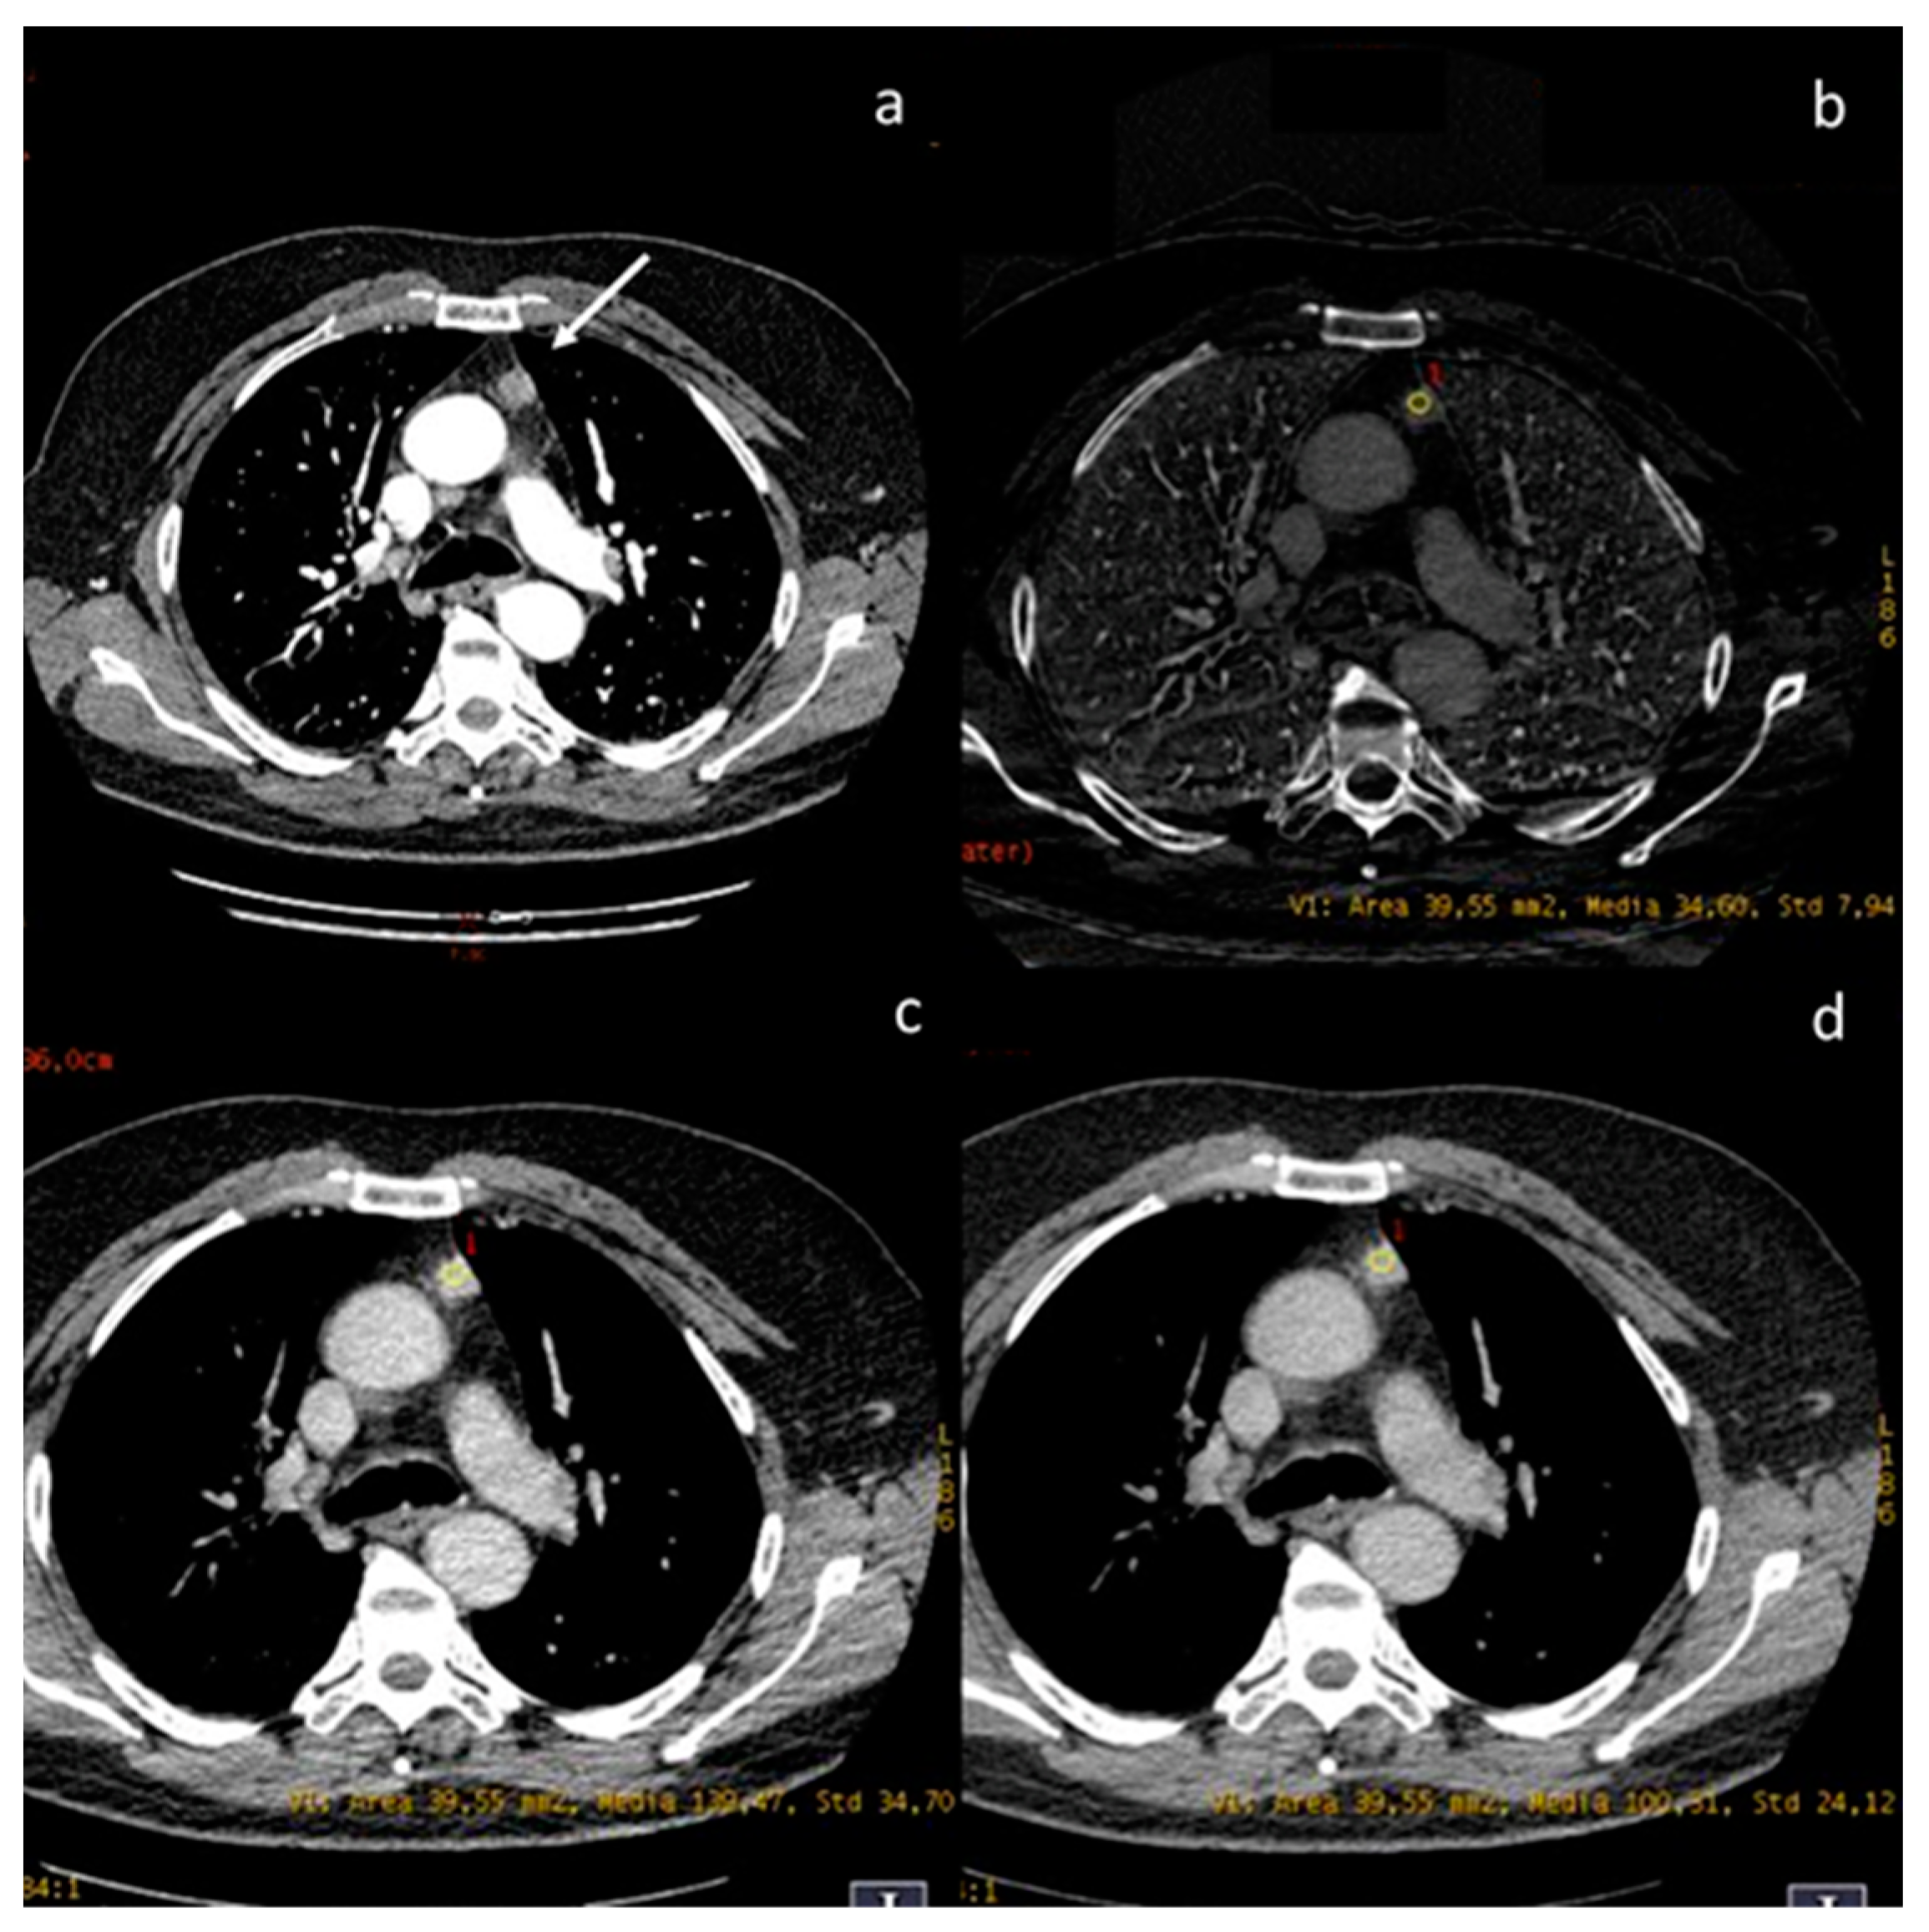

| Chang et al. [63] Prospective study | Korea | To investigate the diagnostic value of DECT in differentiating between low- and high-risk thymomas and thymic carcinomas. | 37 | Discovery CT750 HD; GE Healthcare, Wauwatosa, WI, USA, No C.I. | DECT using a quantitative analytical method based on IC measurement can be used to differentiate among thymic epithelial tumors using single-phase scanning. IHU and IC were lower in high-risk thymomas/carcinomas than in low-risk thymomas. |

| Zhou et al. [64] Retrospective study | China | To explore the utility of DECT parameters in distinguishing thymic epithelial tumours from thymic cysts among lesions <5 cm in diameter. | 56 | Discovery 750HD CT system (GE Healthcare, Madison, WI, USA No C.I. | DECT could distinguish thymic epithelial tumours from thymic cysts (d. < 5 cm). The CT value under 60 keV in the arterial phase has better diagnostic performance. |